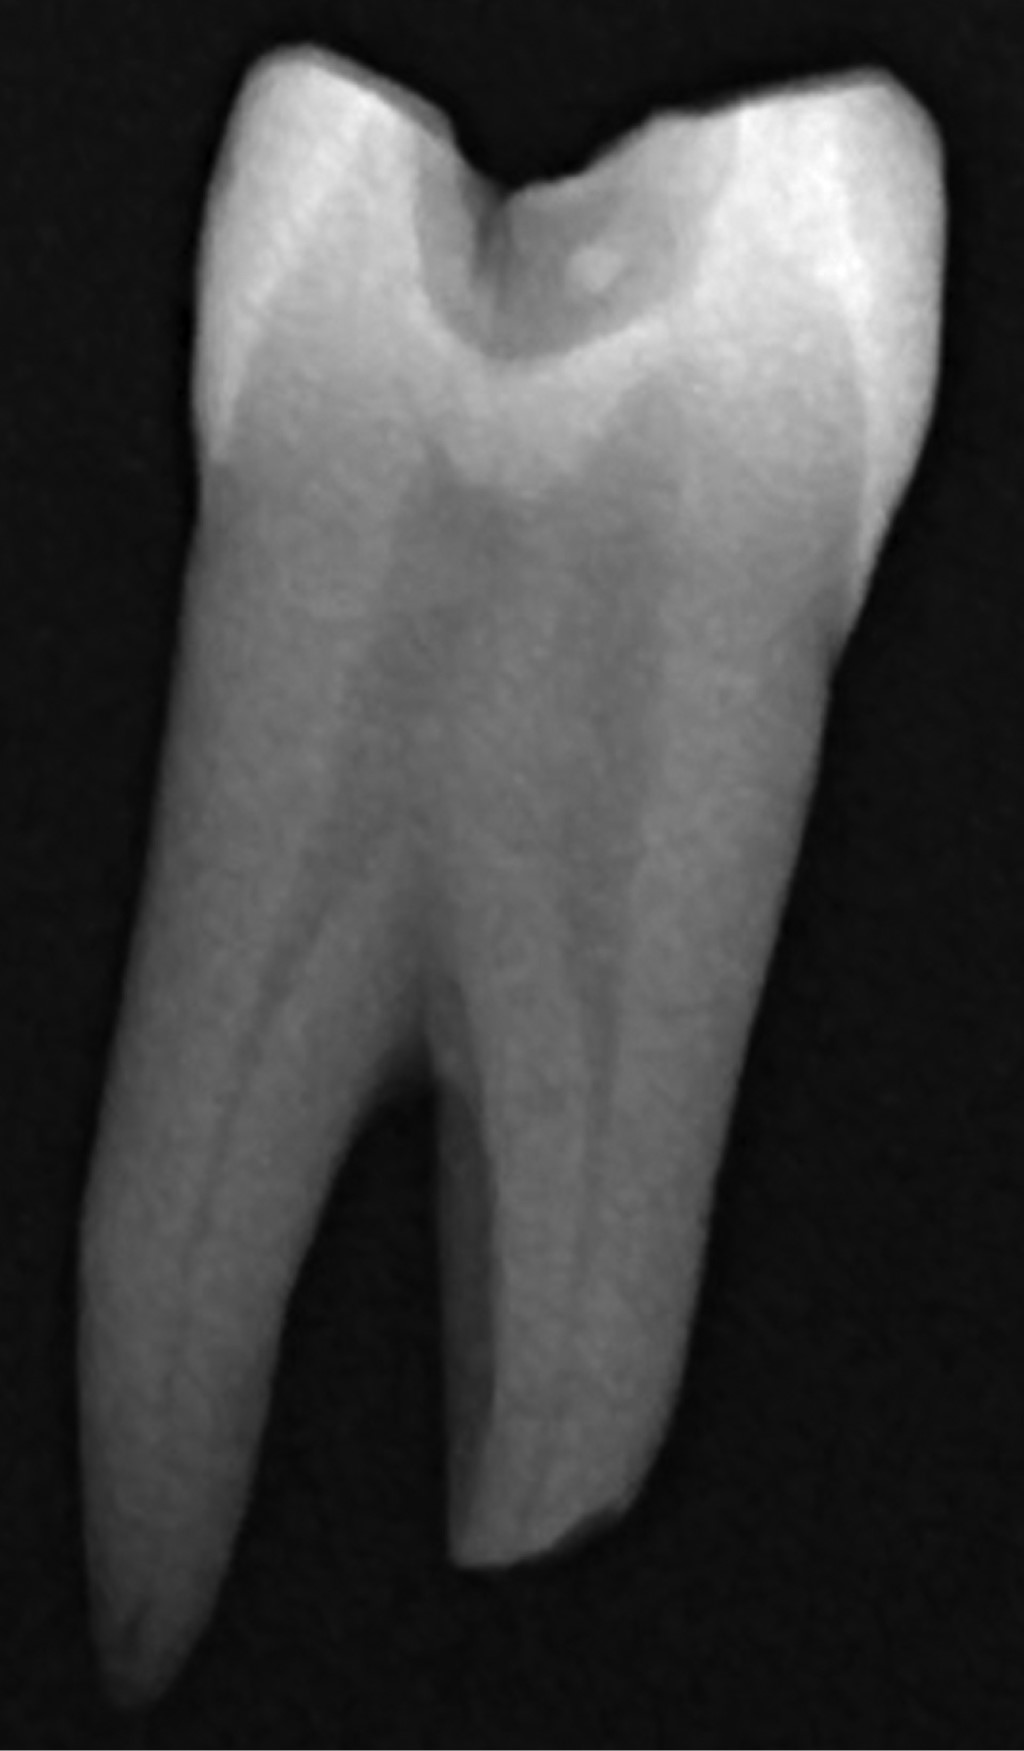

Figure 1

Figure 2

Figure 3

Figure 4